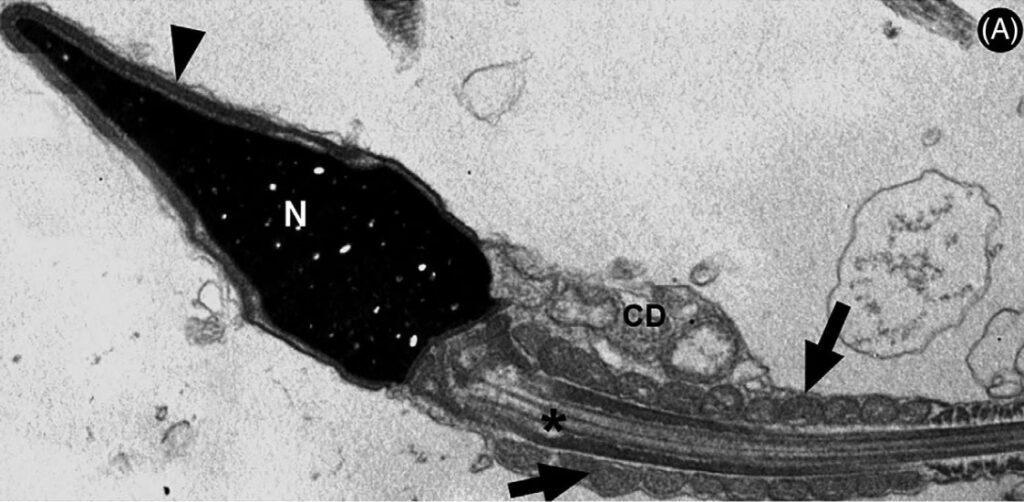

La infertilidad masculina a menudo se reduce a tres problemas principales: un bajo recuento de espermatozoides (oligozoospermia), una mala movilidad (astenozoospermia) o una morfología anormal (teratozoospermia). Los estudios, como los que emplean microscopía electrónica de barrido (MEB), han revelado una realidad alarmante. Muestras de semen que bajo un microscopio óptico convencional parecían normales, al ser analizadas con mayor detalle, muestran un alto porcentaje de espermatozoides con defectos estructurales. Hablamos de colas pequeñas y enrolladas que impiden el nado, piezas medias dobladas que afectan la energía del espermatozoide, o cabezas amorfas y elongadas que comprometen su capacidad para fecundar el óvulo. Estas anomalías no son meras imperfecciones estéticas; son indicadores de un problema profundo en el proceso de espermatogénesis, la fábrica de espermatozoides del cuerpo. Y es aquí donde los factores ambientales entran en juego como posibles causantes de este sabotaje celular.